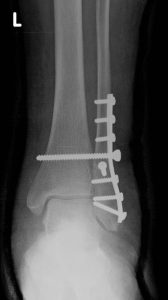

- Skiagrafie

je základní radiologické vyšetření prováděné v ambulantních i lůžkových zařízeních indikované i akutně. Vychází z principu rozdílné absorpce a rozptylu rentgenového záření v jednotlivých tkáních lidského těla ve směru ohnisko – přijímač obrazu. Výsledné zobrazení pak přináší zřetelnou informaci o sledovaných strukturách, kterými jsou skelet, měkké tkáně a struktury s náplní kontrastní látky. Skiagrafický zobrazovací systém umožňuje dosáhnout velkého rozlišení vysokého kontrastu a velkého prostorového rozlišení u zobrazení při možnosti dosažení nízké radiační zátěže pacienta.

Rentgenové vyšetření břicha.Přístrojové vybavení a ukázkové snímky:

- Siemens Multix Fusion, Siemens Ysio Max a Siemens Ysio X.pree